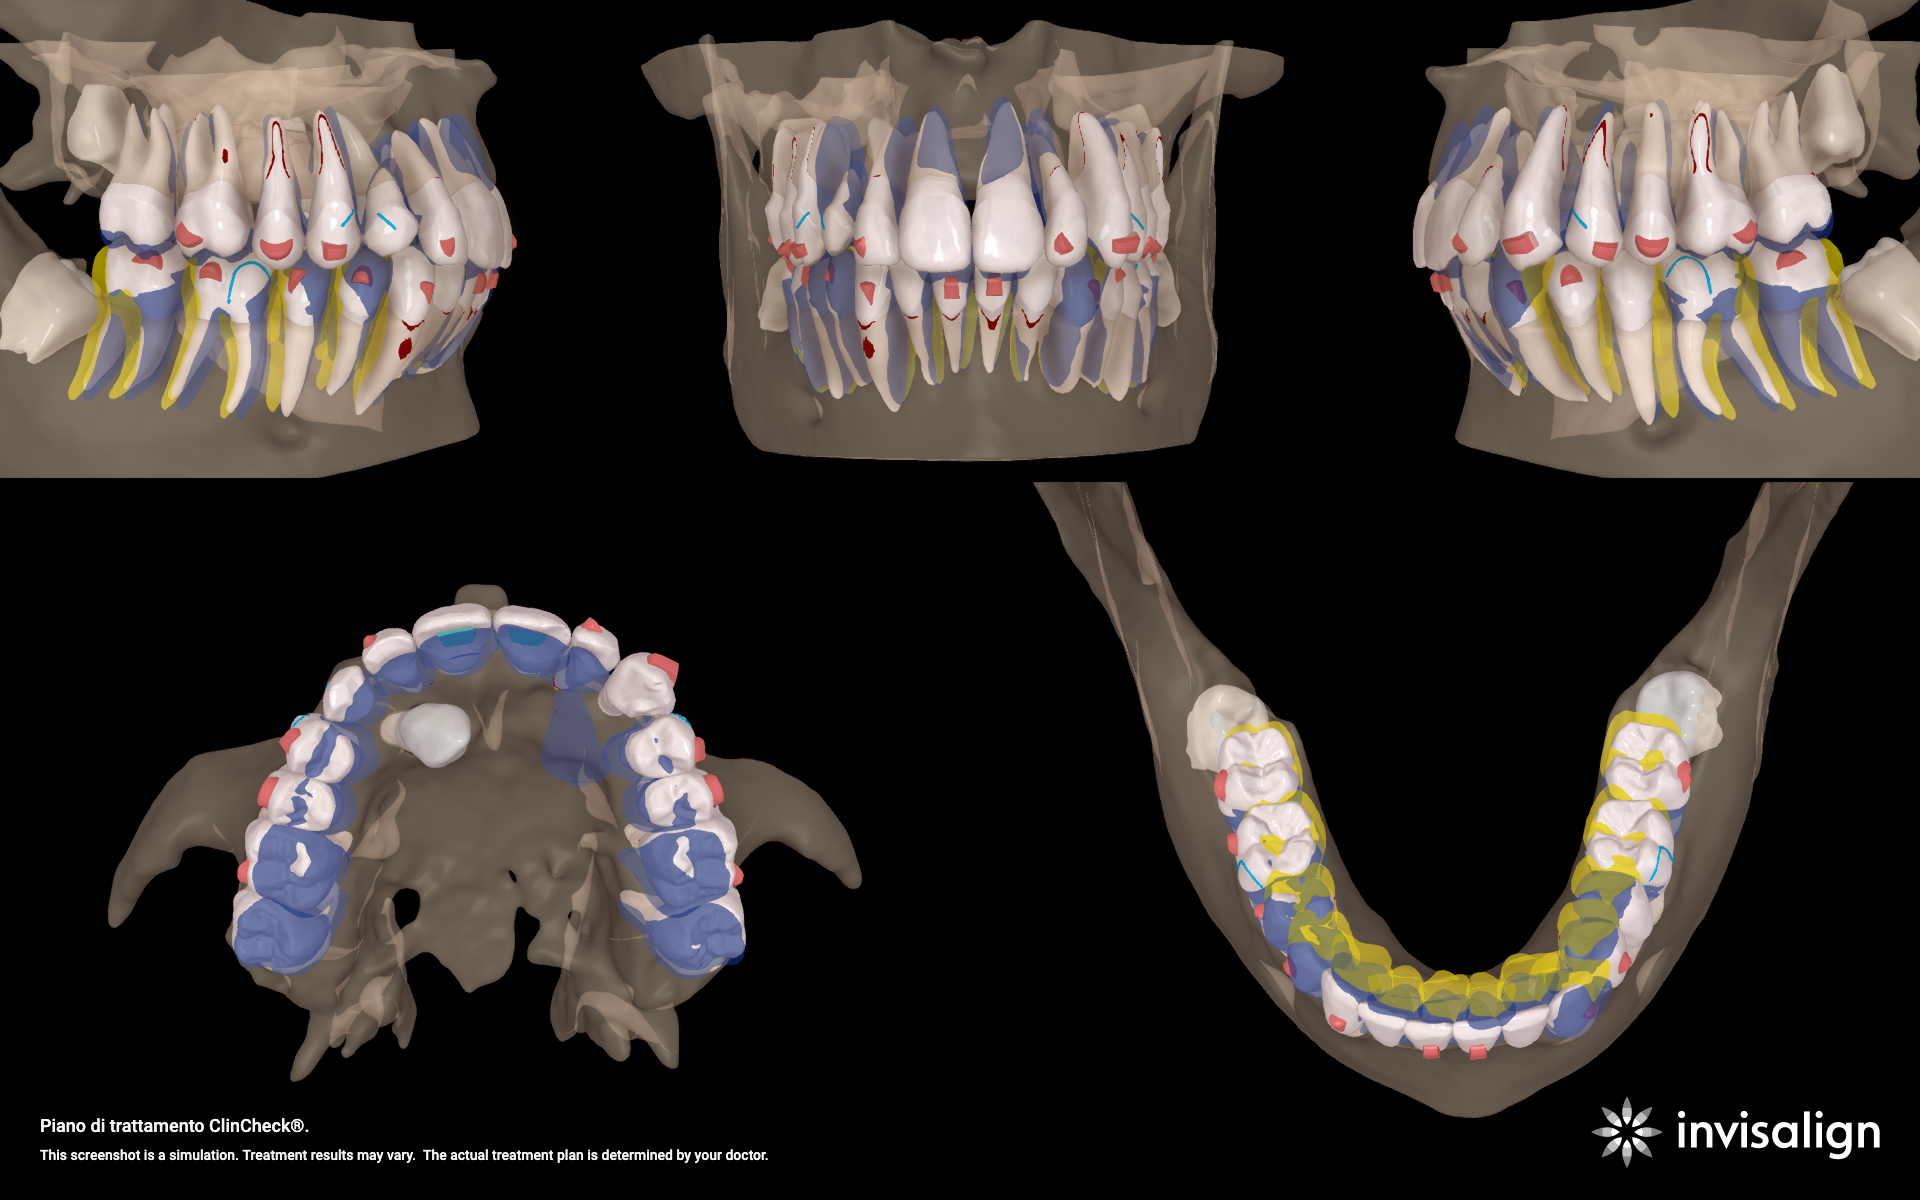

Integrazione digitale e allineatori

Dopo il recupero palatale, è iniziata la fase con allineatori trasparenti, sfruttando il software ClinCheck® Pro e l'integrazione dei dati della CBCT.

Pianificazione e criticità

- Torque: necessità di recuperare il torque positivo sugli incisivi superiori.

- Classe: correzione sagittale tramite distalizzazione sequenziale ( per creare spazio ai canini) e Jump sagittale.

- Gestione del 23: utilizzo di un attachment rettangolare (secondo protocollo Capuozzo et al.) per migliorare il controllo del torque durante la traslazione palato-vestibolare.

- Gestione del 13: data la posizione estremamente palatale, inizialmente non è stato incluso nell'allineatore. È stato avvicinato alla corretta posizione vestibolare mediante un elastico a cavaliere.

Evoluzione del trattamento e refinement

Il percorso terapeutico ha richiesto un monitoraggio costante:

- Fase 23: una nuova scansione ha permesso di includere il 13 negli allineatori. A causa dell'esiguità di spazio, non è stato possibile applicare un attachment rettangolare su questo elemento.

- Fase 40: si è verificato un misfit proprio sul 13. È stato quindi eseguito un terzo set di 32 allineatori per rifinire la posizione e consolidare il risultato.

L'integrazione tra la biomeccanica tradizionale (leve in TMA) e l'ortodonzia digitale (allineatori e CBCT) permette di gestire casi complessi di inclusione con estrema sicurezza. Il protocollo Canine First si conferma una scelta vincente per minimizzare i rischi iatrogeni, mentre la tecnologia ClinCheck® Pro garantisce una predicibilità altrimenti difficile da ottenere in casi di II Classe Divisione 2.